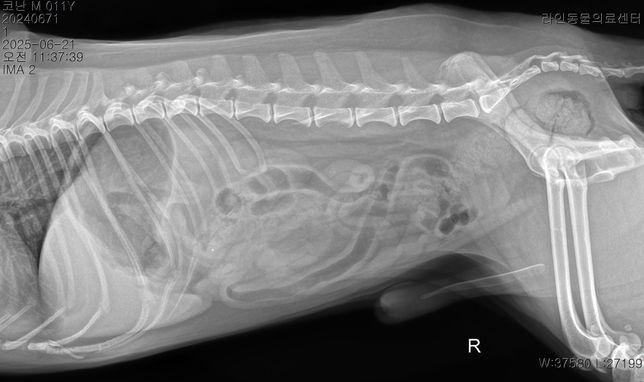

- 반려동물 건강반려동물Q. 강아지 이상증상 이유라도 좀 알고싶습니다..저희 강아지가 어제 아침부터 혀를 내밀고 과호흡에 혀가 보라색이 되고 배가 단단해지길래 바로 응급 병원에 갔더니 별다른 처치는 없었고 산소방에 30분에 있더니 배가 다시 물렁해지며 혀는 여전히 보라색이였으나 엑스레이와 호흡수가 정상이라하여 안정제/진정제 주사를 한대 맞았고 이제 안심을 하고 집에 왓는데 어제 저녁 9시경 애가 물설사와 사진처럼 점액변도 누고 밤 12시경 다시 점액변을 2차례 더 누고 새벽3시경 애가 낑낑거리며 봣더니 배가 다시 단단해져있었고 혀는 괜찮았고 호흡수만 괜찮았지만 하루 종일 잠을 못잤는데 다니던 24시 병원은 전화하니 잘 모르겠다고 솔직한 답변을 주셨고 새벽내내 이리저리 돌아만다녀서 아침에 다른 병원에 가서 엑스레이와 혈액검사 종양검사 등을 하니 저런 결과가 나왔고 이전 병원 엑스레이 사진을 보여드리니 폐침윤이 있어서 다시 엑스레이를 찍어보고 혈액검사도 해보니 심장과 폐문제는 아닌거같다 허리디스크 때문인듯하다 라고 하셨고 복부초음파는 해당 병원 장비가 갑자기 고장이 나서 되지가 않은 그런 상황입니다암은 아니라하고 특이한점은 crp 농도는 정상인데crp 는 13으로 높게 나왔습니다 오늘 찍은 엑스레이상 허리디스크가 심장과 폐 중앙 사이에 있는 허리디스크가 안좋았으며 췌장염은 리파아제 아밀라제가 괜찮다고 아닌거같다고는 하셨는데 cpLi 는 그래서 진행을 안한 상태입니다저도 강아지도 너무 지치는데요 오늘 하루종일 밥을 안먹은 상태이고 주사만 3대 진통제와 스테로이드(쿠싱상관별로없는 약한 스테로이드)를 맞은 상태입니다 대체 어떻게 해야할까요? 정말 허리디스크 때문일까요? 췌장염 가능성은 없을지 여쭤봅니다복부가 단단해지는 증상은 약 3개월전부터있었고 복명음 같은경우도 3개월전부터 있었는데 요즘은 그냥 하루종일 복명음이 들리고 소리도 점점 커지는 느낌입니다.허리디스크라 산책을 하면 안되지만 하도 애가 변을 안누길래 제가 가볍게 산책을 해주면 배가 다시 물렁해지는 그런 상황들이 여러번 있었고 2-3일전부터는 애가 식이알러지 증상도 나타났습니다 고추를 심하게 빨거나 ( 노란 고름이 나와서 항생제도 안에 넣는 세척을 오늘 진행하였고) 평상시에 포비돈으로 희석해서 멸균식염수와 같이 세척해줌에도 작년 9월부터 낫지를 않고 귀와 턱을 미친듯이 긁는 증상들도 있습니다정말 못고쳐도 좋으니 이유만이라도 좀 알고싶은데 병원에 가면 갈수록 저와 강아지는 지쳐만 갑니다한 병원에 계속 다니고 싶어도 첫번째 병원은 엑스레이만 찍고 혈액검사와 복부초음파를 요청하여도 호흡수와 엑스레이가 괜찮다고 그 어떤 처방도 받은것이 없어서 부득이하게 여러 병원들을 다니고 있는 상황인데 병원들이 가깝지도 않아서 차로 최소 1시간 거리들인 상황이라 정말 상상 이상으로 지치는데부디 혈액검사와 증상들을 살펴봐주시고 짐작이 가는 질병이나 췌장이나 대장쪽 문제는 없는지 알고싶습니다정장제와 허리디스크 약을 처방받은 상황이며 일주일동안 약을 먹어보고 그래도 이상하면 췌장이라고 들었습니다 참고로 아밀라아제 리파아제가 정상수치여도 초음파상 췌장에 에코가 있었던 이력이 있으며 심장 같은 경우는 b1 이라고 하고 청진도 잘 안들이기에 여러 병원들이 b2 는 아니라하였고 오늘 찍은 엑스레이에선 폐침윤은 없었습니다 다만 쿠싱이 살짝 의심은 된다고는 하였습니다 멏개월전에는 쿠싱검사시 cor 이 (1-6 이 정상인데 ) 인지 9 정도 나왔는데 몇개월후 오늘은 7.5 로 되었습니다 • T4-6 vertebrae의Rt. caudal articular process의defect 확인됩니다. (→)• T13-L1 vertebrae의IVDS(intervertebral disc space)가주변에비해좁게확인됩니다.(→• T13-L1 vertebrae의IVDS가주변에비해좁게확인되어IVDD 가능성고려됩니다. 신경계검사등추가적인신체검사추천되며, 신체검사상특이소견또는임상증상확인될경우척수실질평가를위한MRI 검사가추천될수있습니다.• T4-6 vertebrae의Rt. caudal articular process의dysplasia 확인되며, congenitalanomaly로고려됩니다. 이는, incidental finding으로고려되나, 척추의불안정성을야기하여IVDD를유발할수있습니다마지막 사진은 저희 강아지 작년 ct 촬영 사진입니다